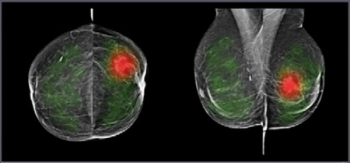

Emerging breast ultrasound research showed the use of computer-aided diagnosis (CAD), powered by deep learning, led to 24 percent and 36.9 percent improvements in accuracy and specificity, respectively, in the use of BI-RADS classifications by radiologists without breast ultrasound expertise.

Adjunctive use of an artificial intelligence (AI) software demonstrated nearly equivalent sensitivity and over 28 percent higher accuracy in comparison to radiologist assessment of breast ultrasound images for breast lesions, according to new research presented at the recent Society of Breast Imaging (SBI) conference.